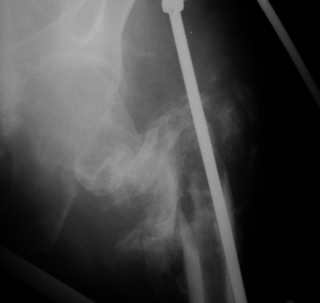

[Ortho] Последствия чрезвертельного перелома бедренной кости, часть 2

рис. 4, 5, 6.

см. "Последствия чрезвертельного перелома бедренной кости, часть 1".